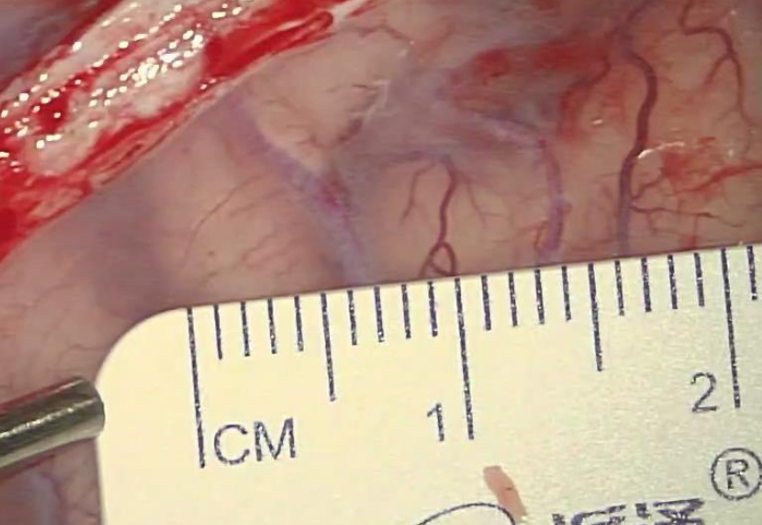

最后在脑沟里翻出一根稍粗点的血管,但是一端扎入更深处,一端马上分叉,能利用的范围很小:

缝合空间有限: